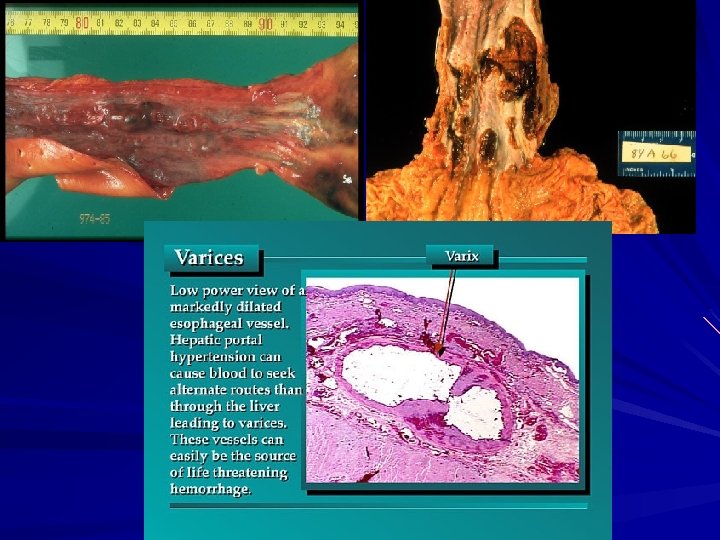

Varices Portal hypertension collateral bypass channels (wherever the portal and caval systems communicate) The increased pressure in the esophageal plexus produces dilated tortuous vessels called varices. Two-thirds of all cirrhotic patients and are most often associated with alcoholic cirrhosis. No symptoms until they rupture. Massive hematemesis